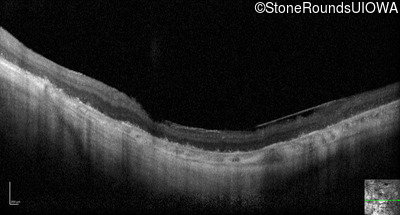

Optical Coherence Tomography - Right - Hand Motion sc

Exemplar / OCT Stack